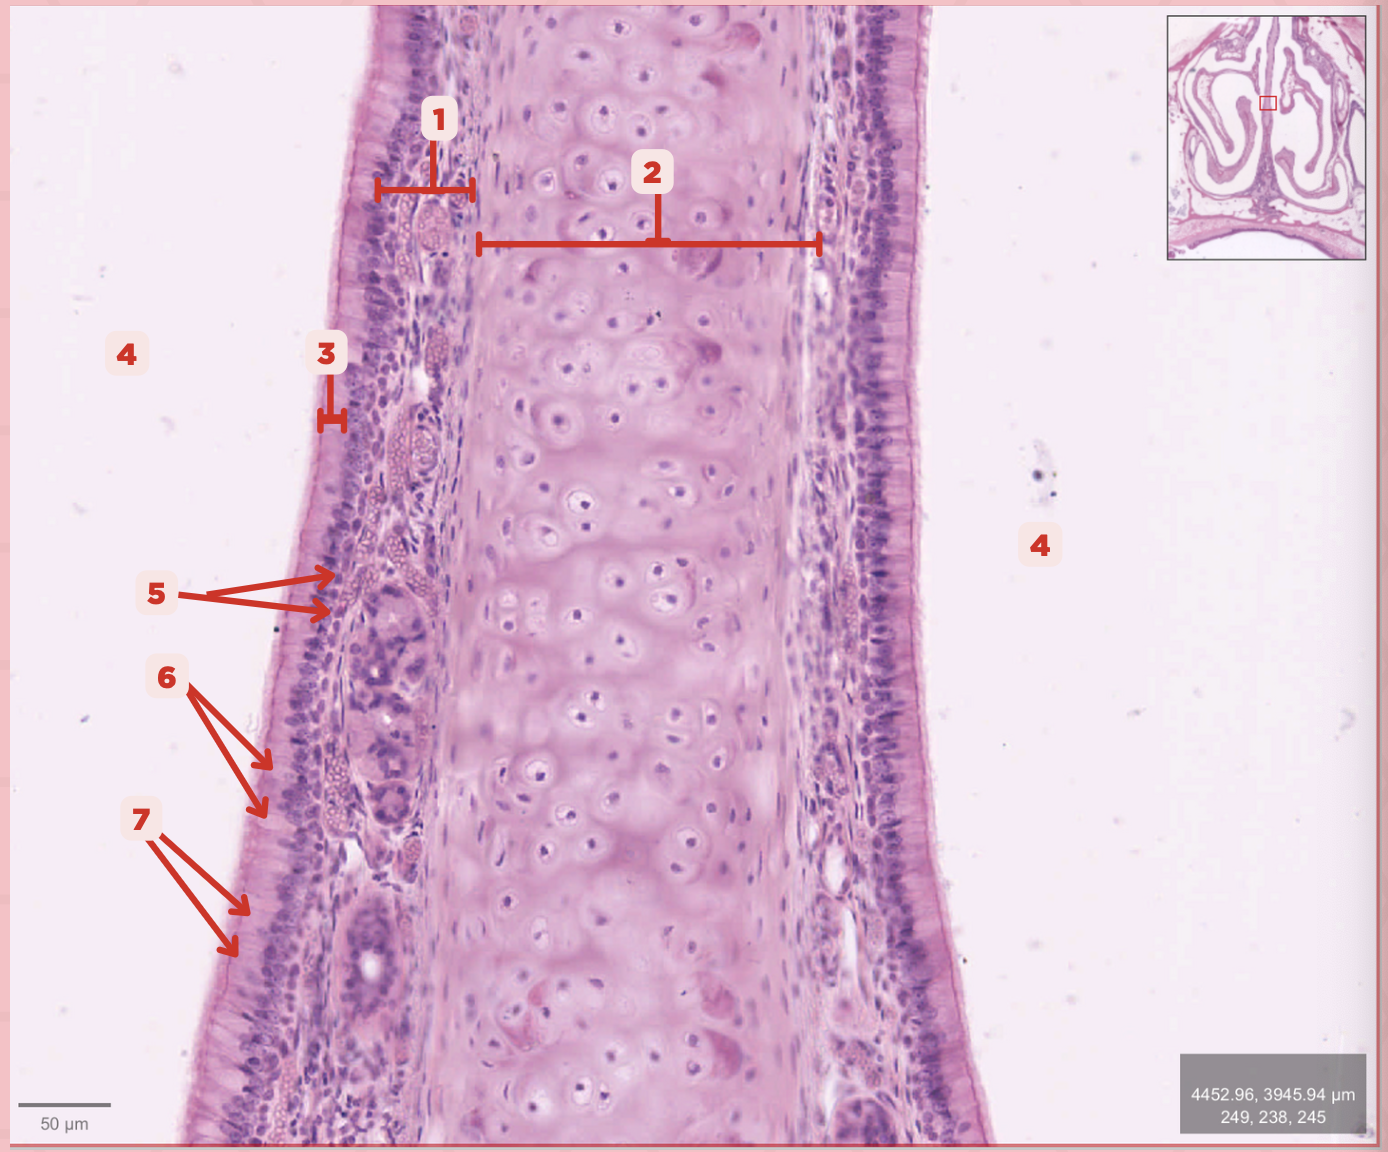

Identify the structure labeled as 1.

Hyaline Cartilage

Identify the structure labeled as 2.

Respiratory Epithelium

Identify the structure labeled as 3.

Nasal Cavity

Identify the structure labeled as 4.

Basal Cells

Identify the structure labeled as 5.

Goblet Cells

Identify the structure labeled as 6.

Ciliated Columnar Cells

Identify the structure labeled as 7.

Adipose tissue

What type of tissue is sometimes seen between the bony spicules?

Serous and Mucous Glands

What glands are present in the Lamina Propria?